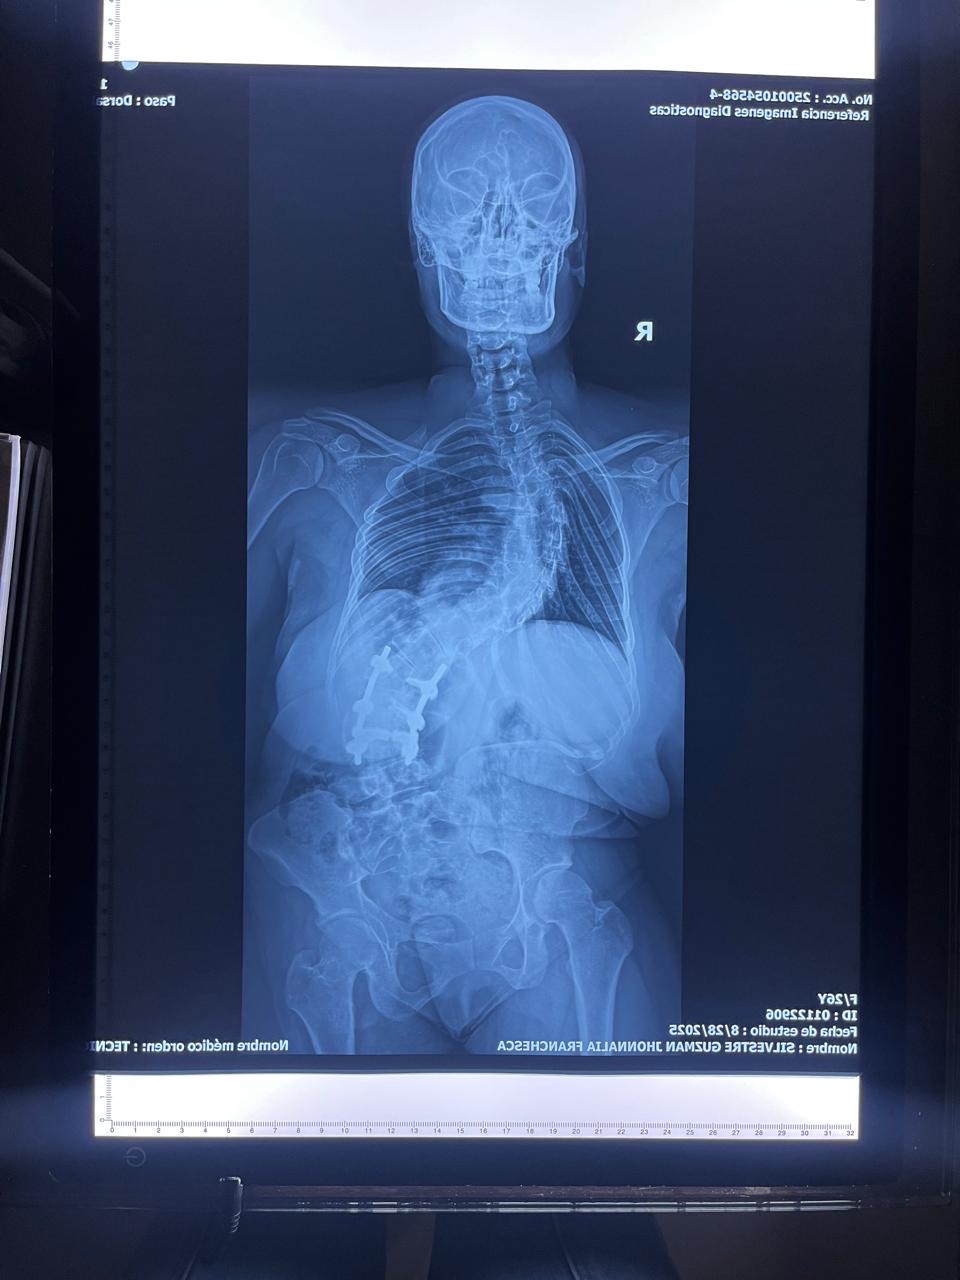

Quiero contarte un poco sobre mi historia: desde la adolescencia, vivo con una condición llamada escoliosis dorso-lumbar, en la cual la columna se curva de manera anormal formando una S. En mi caso, la curva superior se dobla hacia el lado derecho y la inferior hacia el lado izquierdo. Esto no solo afecta la forma de mi columna, sino que también comprime órganos vitales, provocando dolor constante y dificultades en mi respiración.

Desde los 11 años he pasado por 5 cirugías de alto riesgo intentando mejorar mi calidad de vida, pero la enfermedad ha seguido avanzando. Actualmente, aunque tengo 25 años, mis pulmones presentan un desgaste propio de más de 40 años debido a la compresión de mi columna. Mi cuerpo está físicamente afectado, vivo con dolor crónico diario, y cada día se hace más difícil realizar actividades normales.